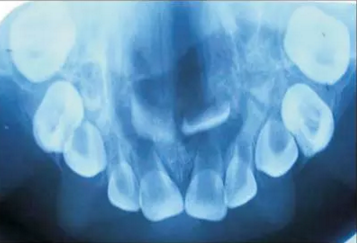

口內咬合片可見上頜3×4cm大小低密度影,上頜中切牙恒牙胚移位。